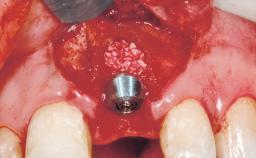

Late Placement of an Implant in a Maxillary Left Central Incisor Site

Type of Implants Two-Piece

Augmentation Materials Xenogenous|Membrane

Soft Tissue Grafting Simultaneous

Placement Protocol Early or late implant placement